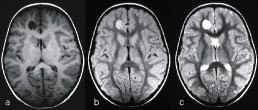

Selv om MR-teknikken kan fremstille samme anatomi med mange ulike bildekontraster, finnes det likevel patologiske prosesser med vevsegenskaper (f.eks. protontetthet, T1- og T2-verdi) som er så lik omgivende normalt vev at de derfor vanskelig lar seg detektere. Tilførsel av kontrastmiddel kan øke deteksjonen og også bidra til å karakterisere en lesjon. Det finnes mange ulike kontrastmidler for MR, men felles for de aller fleste er at de forkorter T1- og T2-relaksasjonen til omgivende protoner. Kontrastmidler som forkorter T1, fører til økt signal på T1-vektede bilder (positive kontrastmidler) (fig 9), mens kontrastmidler som forkorter T2, gir redusert signal på T2-vektede bilder (negative kontrastmidler).

Et enkelt indusert strømsignal inneholder ikke nok informasjon til at man ved hjelp av Fourier-transformasjon kan rekonstruere et bilde. Det kreves vanligvis mange strømsignaler og følgelig mange radiobølgepulser. De ulike gråtonene i bildet, bildekontrasten, er bestemt dels av de ulike vev som avbildes, dels av en rekke operatørbestemte parametere, som blant annet tidsintervallene mellom radiobølgepulsene og radiobølgenes styrke og varighet (som bestemmer flippvinkelen). Ved riktig valg av parametere kan ulike egenskaper ved vevene fremheves i bildet (3, 4). Man kan la gråtonene være bestemt av vevenes protontetthet, men også av andre egenskaper som for eksempel vevenes T1- eller T2-verdi. T1 er en tidsparameter som forteller hvor fort det reduserte overskuddet av parallelle protoner gjenoppbygges etter en radiobølgepuls. T2 er en annen tidsparameter som forteller hvor fort nettomagnetismen i x-y-planet forsvinner etter en radiobølgepuls. Begge disse parametrene er bestemt av fysiske og kjemiske egenskaper ved vevene og vil følgelig variere fra vev til vev (begge er relatert til molekylenes mobilitet). I et såkalt T1-vektet bilde er gråtonene langt på vei bestemt av forskjeller i T1 mellom vevene (kortest T1 gir kraftigst vokselmagnetisme og derfor lysest gråtone), og i et T2-vektet bilde er gråtonene bestemt av forskjeller i T2 (lang T2 gir kraftigst vokselmagnetisme og derfor lysest gråtone) (fig 8). Strømning i en væske vil også påvirke signalstyrken fra væsken. Blod i blodårer eller hjertet har således pga. sin bevegelse ofte en gråtone som gir god kontrast mot stasjonært vev, enten svart eller hvitt avhengig av den teknikken som brukes. Andre vevsavhengige parametere som bildemess

ig kan fremheves av ulike MR-teknikker, er diffusjon, perfusjon, blodets oksygeneringsgrad og temperatur.